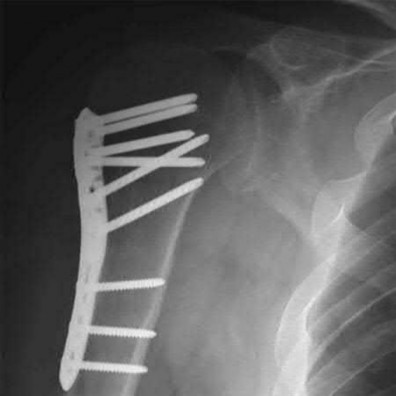

A 64-year-old woman is thrown off a horse, sustaining the injury shown in Figures A and B. She undergoes surgical fixation as seen in Figures C through E. What is the most commonly reported complication of this procedure?

The patient in the scenario has a 2-part proximal humerus fracture treated with a locking plate as seen in Figures A-E. The most common complication with the use of this implant is screw penetration. The terms screw cut out and penetration are often used interchangeably in the literature with cut out appearing more frequently in reports regarding intertrochanteric fractures.

Owsley et al retrospectively reviewed 53 proximal humerus fractures treated with locking plates and the same post-operative protocol. The most common complication was screw cut out or penetration, followed by varus displacement. They concluded that 3 and 4-part fractures in patients over 60 years have a higher incidence of failure.

Agudelo et al retrospectively reviewed 153 patients at a level-one trauma center treated with proximal humerus locking plates, investigating modes of failure for the implant. They determined that varus malreduction (head-shaft angle